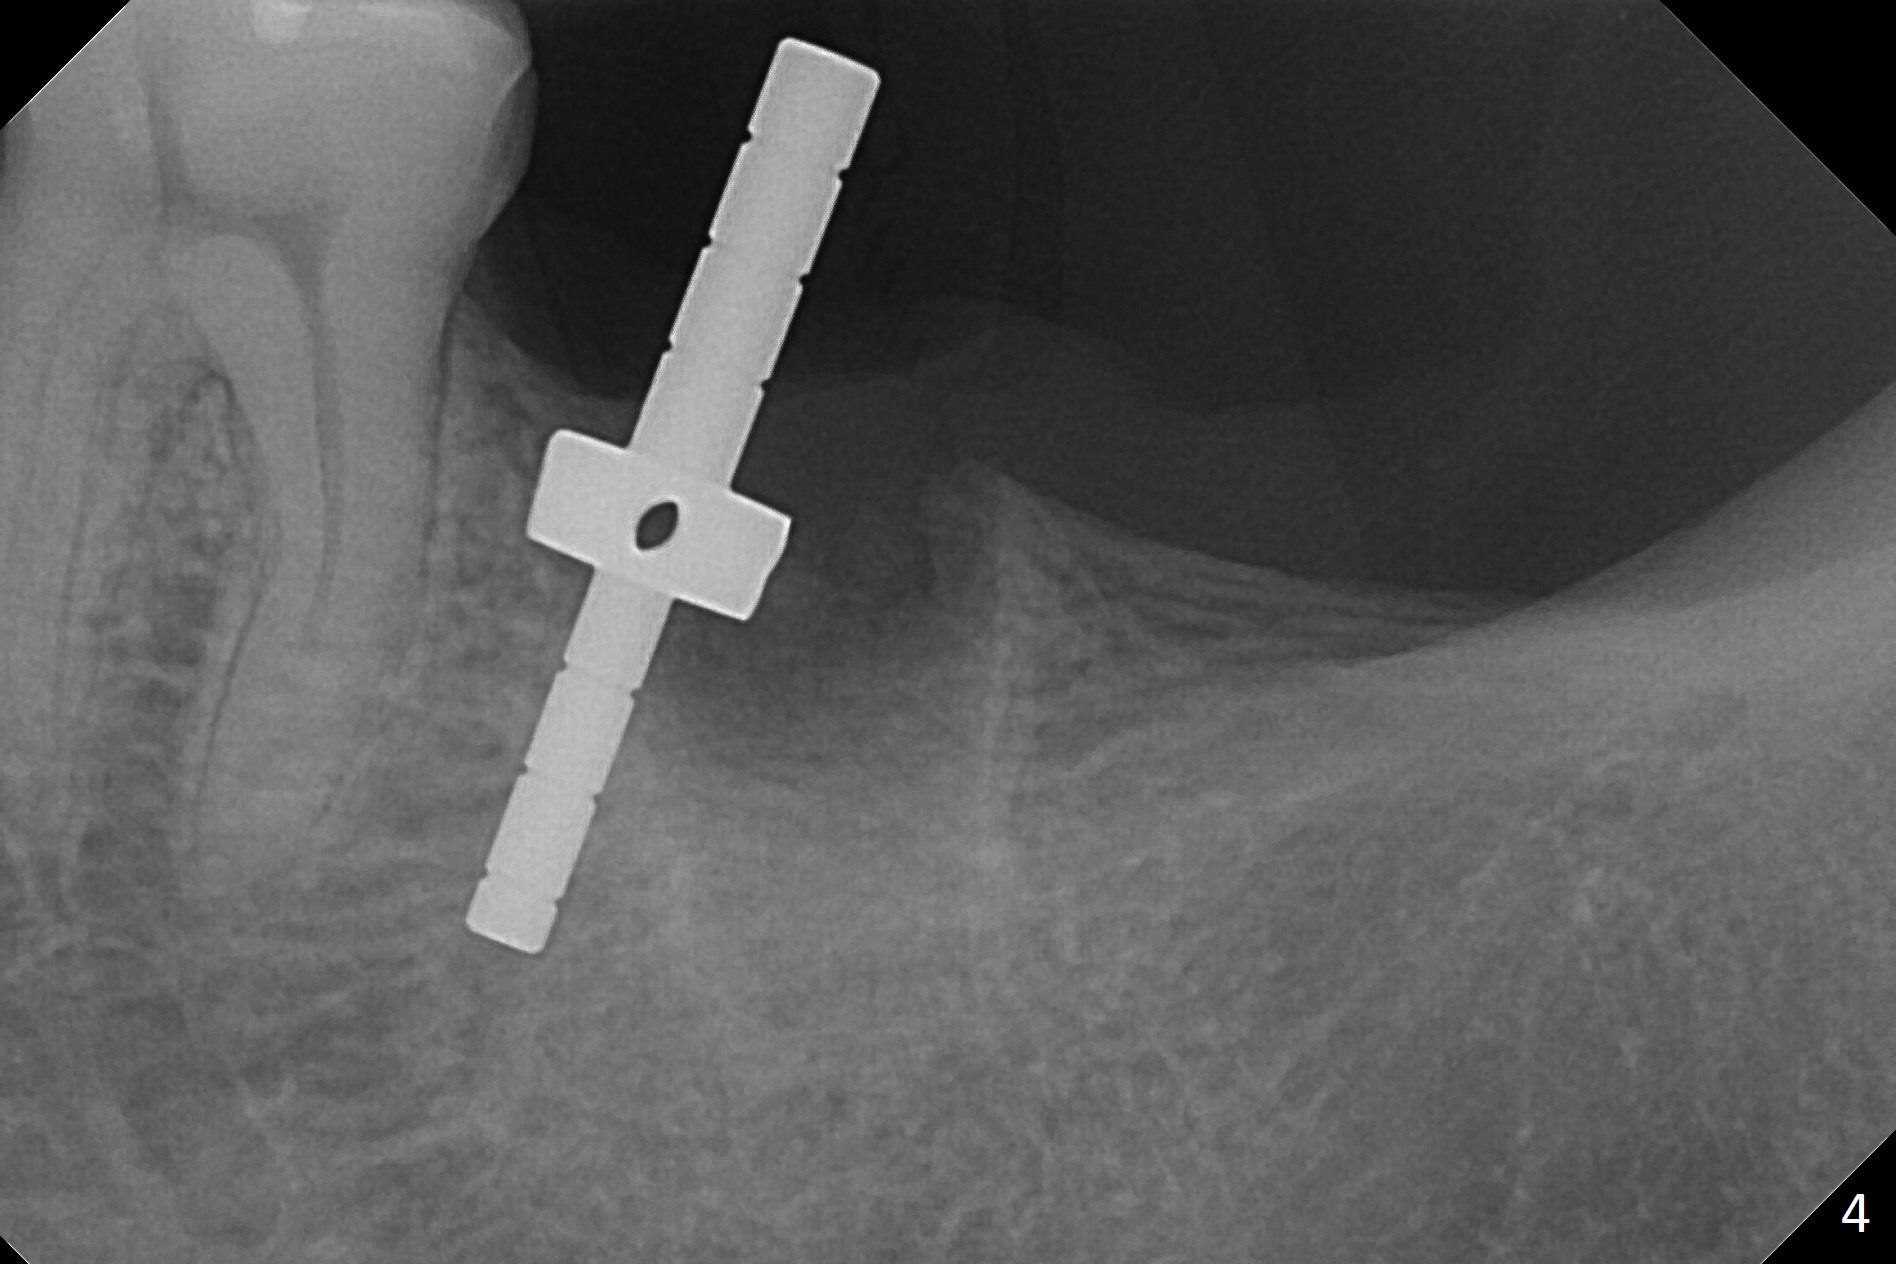

The initial osteotomy with 1.6 mm drill (Fig.4 with parallel pin) needs to be moved distally with Lindamann bur.